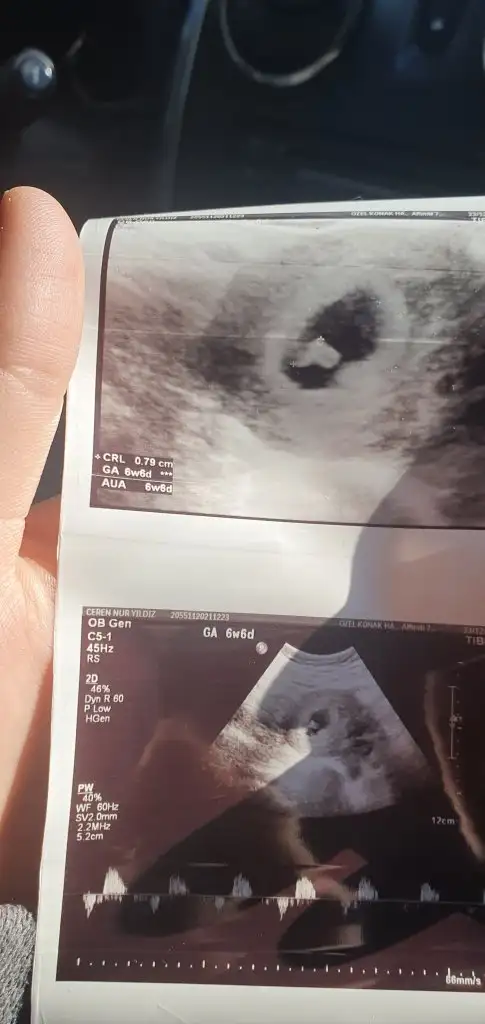

Bebegin Kesedeki Konumuna Göre Cinsiyet Tahmini

bebegin7-8 haftalıkkenki usg resimine direkt baktıgınızda;

bebek kesenin soluna yakınsa bebek erkek,

sagına yakınsa kız.